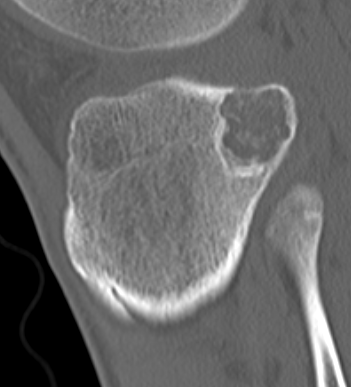

X-ray

Well defined eccentrically located epiphyseal lesion

- thin sclerotic reactive rim

- may have calcification

CT

Evaluate articular surface integrity / compromise

Identify chondroid matrix